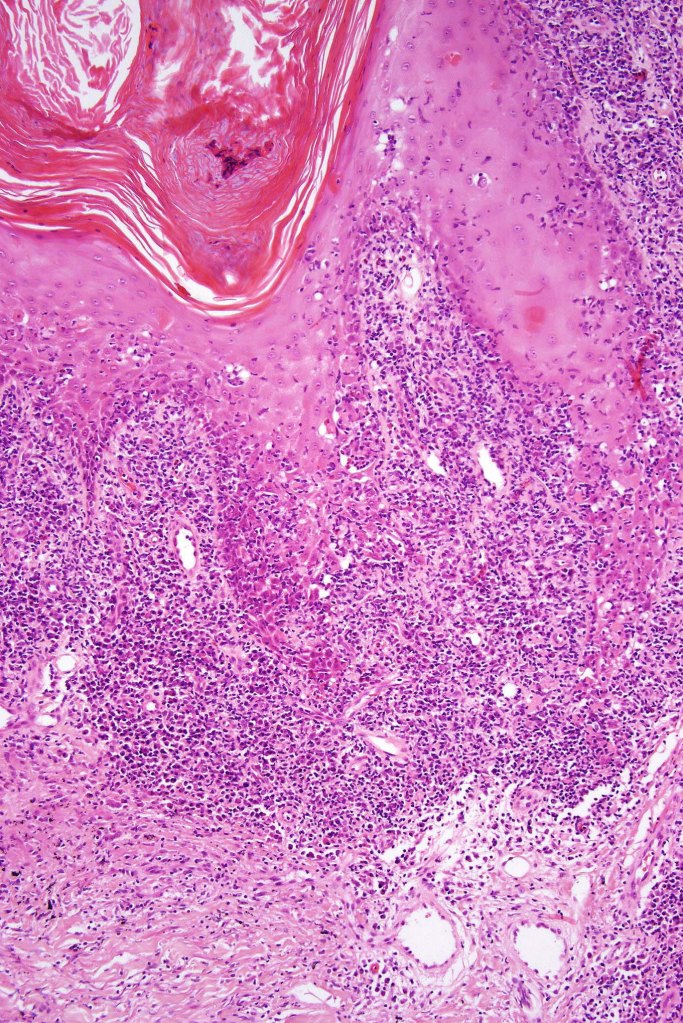

Histological features

•Epidermal involvement often absent

•Follicular infiltration by atypical lymphocytes & Sézary cells

•+/- mucinosis

•+/- syringotropic lesions

•+/- basaloid follicular hyperplasia

•Eosinophils sometimes conspicuous (eosinophilic folliculitis-like appearance)

•Granulomatous inflammation secondary to follicular destruction

•Large cell transformation occasionally present